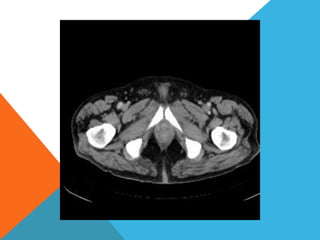

El paciente presentó síntomas de sangrado digestivo y pérdida de peso. Exámenes revelaron gastritis crónica asociada a H. pylori. Un tumor fue descubierto en una colonoscopia normal. La cirugía removió un tumor fibroide solitario, una rara neoplasia mesenquimal que usualmente crece lento y tiene bajo potencial de malignidad. El pronóstico después de la remoción quirúrgica es generalmente bueno.